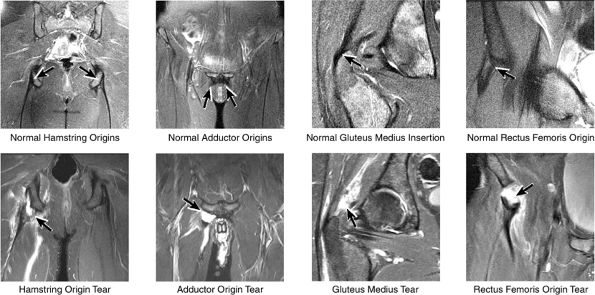

![]() |

FIGURE 3.31 / Femur and Acetabulum.

FIGURE 3.32 / Hip Cartilage.

FIGURE 3.33 / Labrum.

FIGURE 3.34 / Muscle and Tendon Insertions.